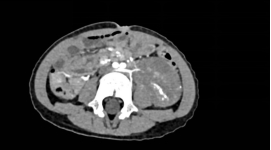

该患儿反复腹痛难忍,家属遂携其前往广元市第一人民医院就医。经检查发现腹腔内长有一直径约10厘米的巨大肿瘤,肿瘤上极达左侧肾门、下极达左侧髂总动脉分叉平面,可见腹主动脉下端一分支动脉供血,肿瘤已严重挤压肾脏、输尿管、肠道等重要脏器,若不及时手术,将危及生命。但患儿年龄仅3岁,器官娇嫩、耐受度低,且肿瘤与腹腔大血管紧密粘连,手术分离难度极高,稍有不慎便可能引发大出血等致命风险,治疗挑战重重。

面对这个棘手问题,医院立即启动儿童重症病例多学科协作机制。由分管副院长何东权主持,胃肠外科·小儿外科牵头,联合影像科、麻醉手术中心、心胸血管外科、儿科、肿瘤科、泌尿外科、重症医学科开展多轮会诊。影像科通过高清三维成像,精准标注肿瘤边界、血管分布及与周围脏器的关系,为手术规划“导航图”;麻醉手术中心针对患儿生理特点,定制“精准麻醉”方案,全程守护心肺功能稳定;重症医学科提前备好术后监护设备,做好应急保障预案。